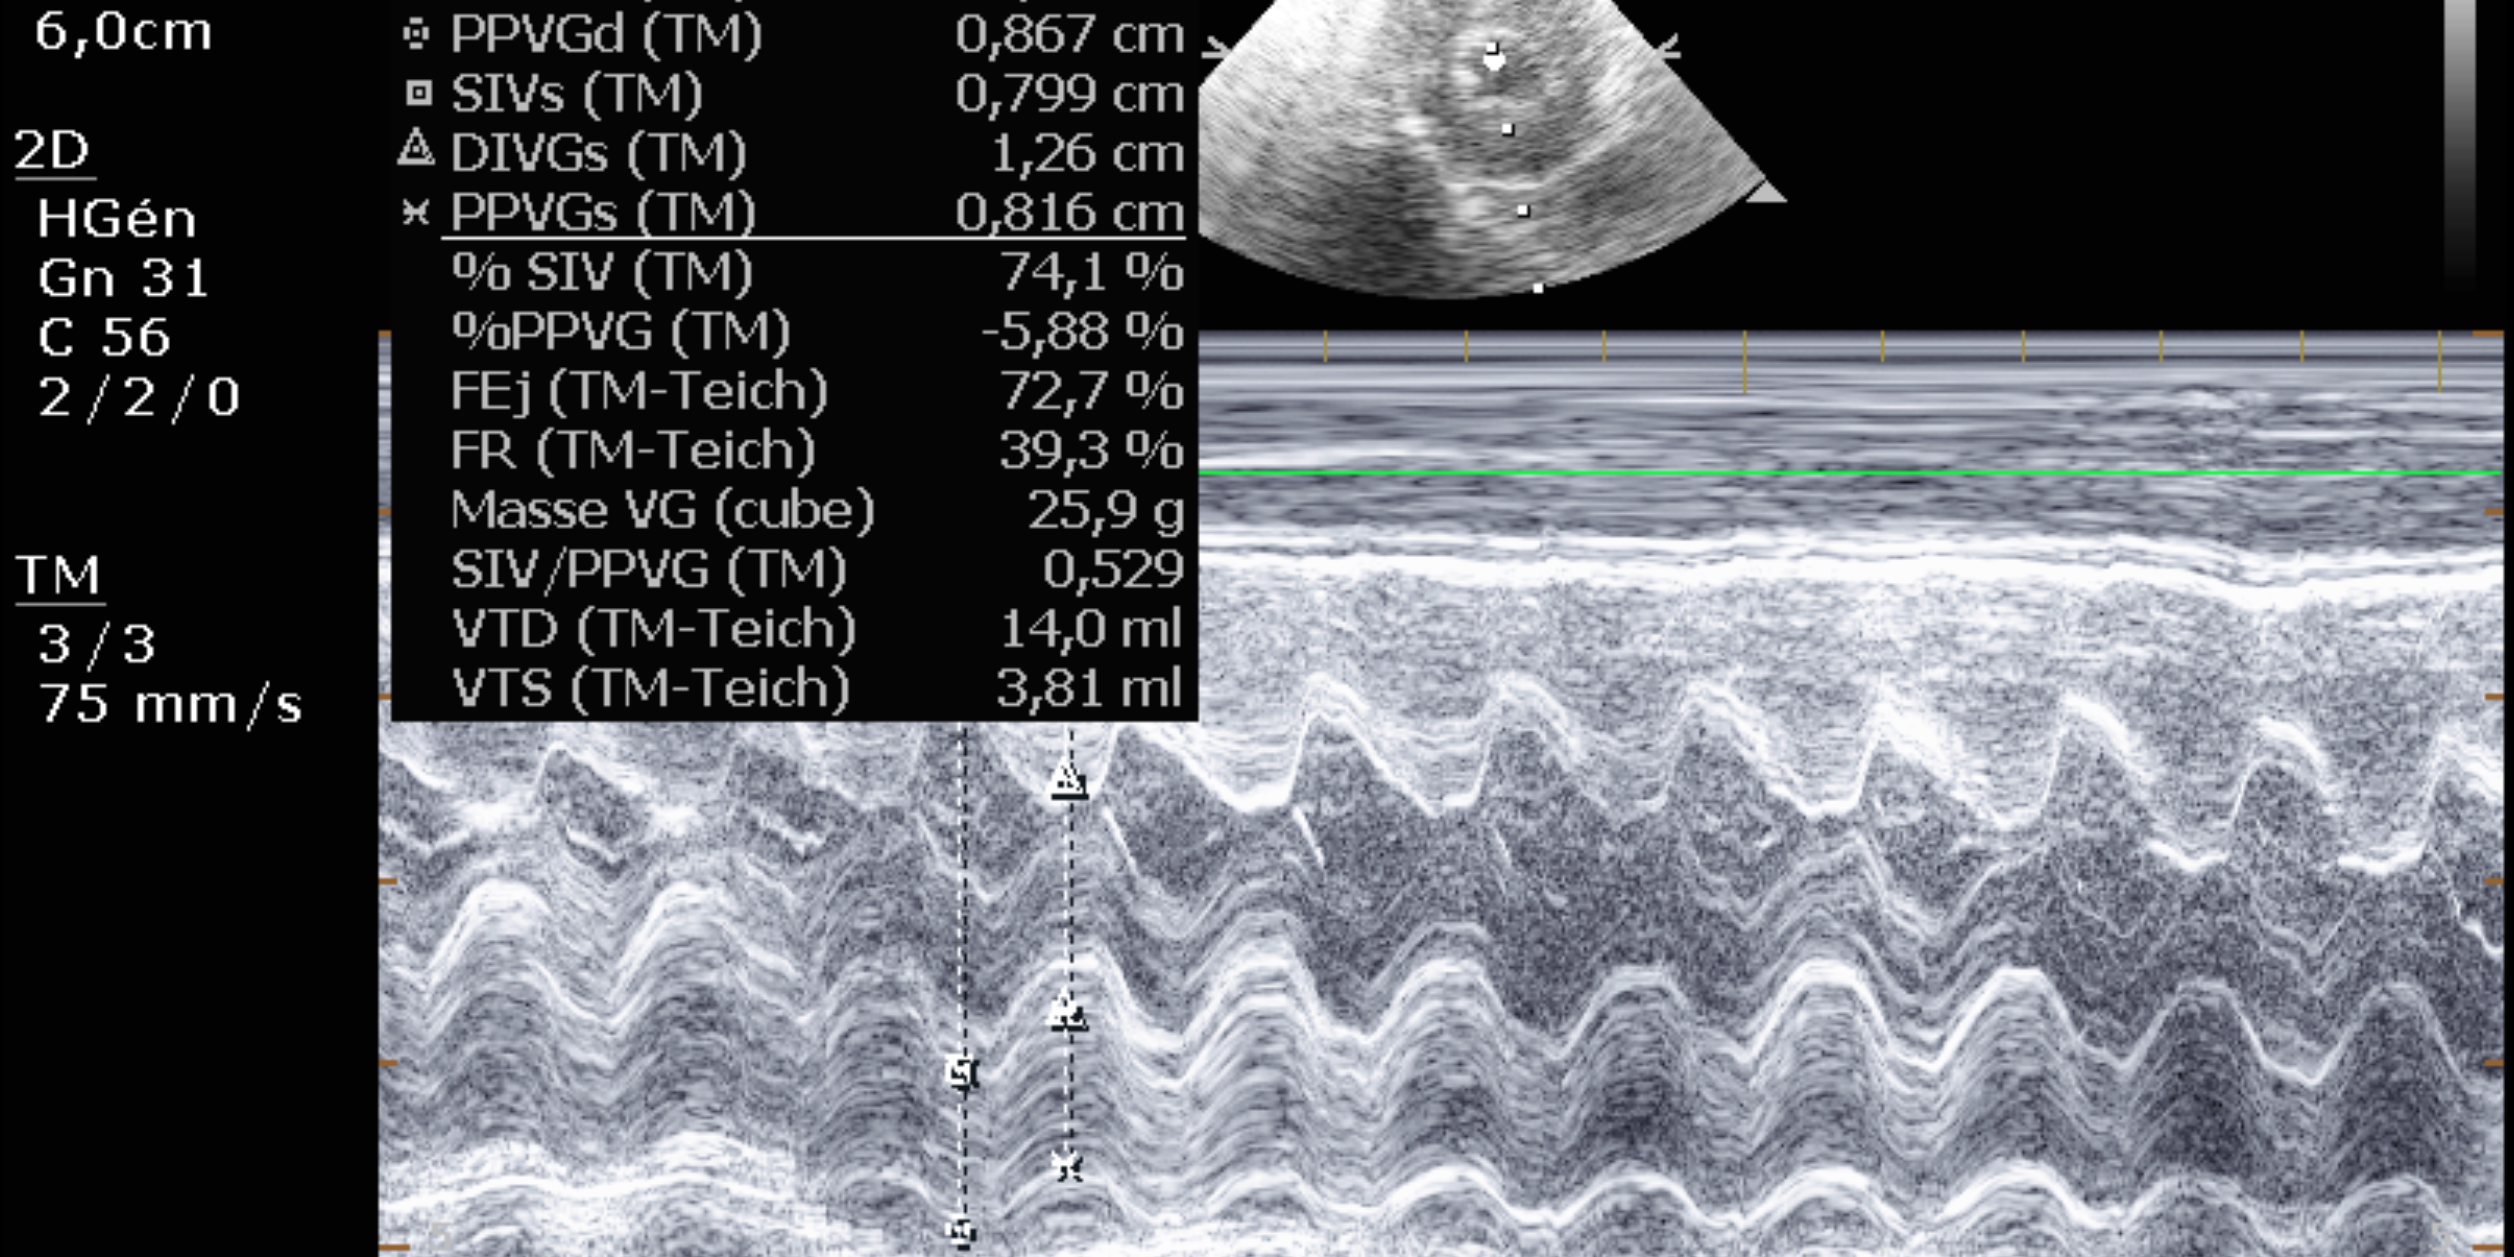

L’échographie du cœur est diagnostique car elle permet de mesurer l’épaississement du muscle cardiaque.